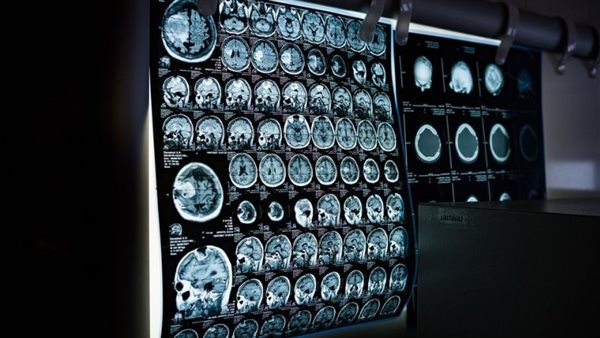

دراسة: الالتهاب الجهازي مرتبط بارتفاع مخاطر الإصابة بالخرف

وجد باحثون بريطانيون أن التهاب الجهاز المناعي الفطري في الجسم، مرتبط بخطر الإصابة بالخرف، وذلك خلال دراسة نشرت في مجلة PLOS ONE.

الالتهاب الجهازي مرتبط بارتفاع مخاطر الإصابة بالخرف